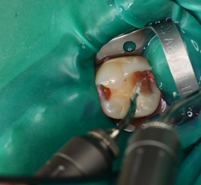

エナメル質はErレザーで除去します。 |

虫歯(感染象牙質)は切削ドリルを使用せず、エキスカベーター(手用切削器具)で慎重に除去します。理由は健康な歯を無駄に削るのを避けられるからです。しかし非常に時間がかかります。治療効率を求められる保険診療では、切削ドリルを使うことが圧倒的多いです。 |